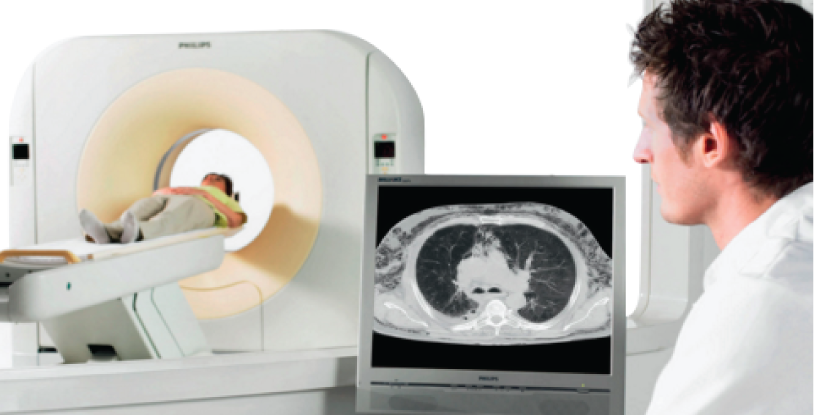

Rayos X, Digitalizadores (CR), Digital directo (DR), Flat Panel (DX), RX Portatiles, Mamografos, Ecografos, Tomografos, Arcos en C, Resonadores, Quemadores de CD, Inyectores, Medios de contraste, Impresoras termicas, Papel de ecografía, Gel, Películas radiográficas analogas y digitales, RIS-PACS, Plomados.

Mantenimiento Correctivo y Preventivo de equipos Radiológicos, Teleradiología, Alquiler de equipos Radiológicos, Adecuación de salas, Asesoria para los servicios de imagenología.